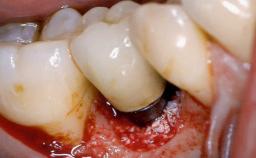

Surgical Management of Peri-Implantitis: Open-Flap Debridement with Seven-Year Follow-up After Treatment

This case describes both a surgical and an anti-infective approach for the management of peri-implantitis, including treatment of the entire dentition to eliminate any deep periodontal pockets that could serve as reservoirs for bacterial re-colonization at the implant site. A 65-year-old female patient was referred to the periodontist in 2013 for assessment and management of an infection at implant 12. On examination, probing depths at implant 12 were 11 mm with suppuration and bleeding on probing.